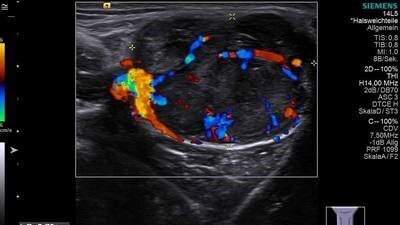

Die Aussagekraft des Ultraschalls kann erheblich durch die Anwendung des Dopplereffekts erhöht werden. Die sich in Gefäßen bewegenden Blutkörperchen können dann auf dem Bildschirm richtungsbestimmt farbkodiert wiedergegeben werden, was als Farbdopplersonografie bezeichnet wird. Verwendet man zusätzlich noch Kontrastmittel, wird die Durchblutung von Kapillaren sichtbar. Der Ultraschall ist das am häufigsten genutzte bildgebende Verfahren in der Medizin. Ein wesentlicher Vorteil gegenüber den in der Medizin ebenfalls häufig verwendeten Röntgenverfahren, wie etwa Computertomografie, liegt in der Unschädlichkeit der eingesetzten Schallwellen; diese sind sogar für Kinder und Schwangere völlig ungefährlich und schmerzfrei.